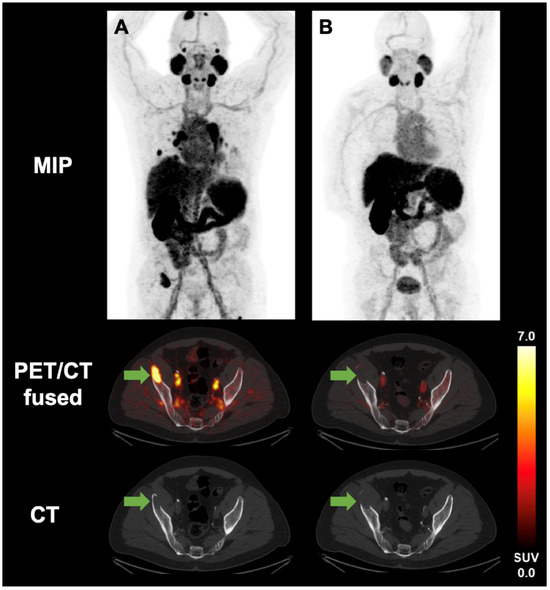

3.2. Image Analysis